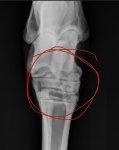

I had my hairy cob out to the vets today for xrays as we have noticed he hasnt been wanting to go forward on the left rein but seems fine on the right. The vet xrayed and has found that the gaps in his hocks are not as wide as they should be and the way his legs are means his hocks dont go underneath him properly. He has never showed any signs of lameness and i dont know how he seems to stuffle on his left but not his right.

Now the plan going forward from the vet is to look into back shoes as he is currently barefoot and work with the physio to build his core and the area surrounding his pelvis so there is less pressure on his legs. The question is has anyone ever experienced, is there livht at the end of tunnel where he could be a ridden pony (he is only 5) if yes is there anything else we can do to help him? Vet is thinking either just poor confirmation has caused this or his feet being in a very bad way before I got him. Any help suggestions would be great please